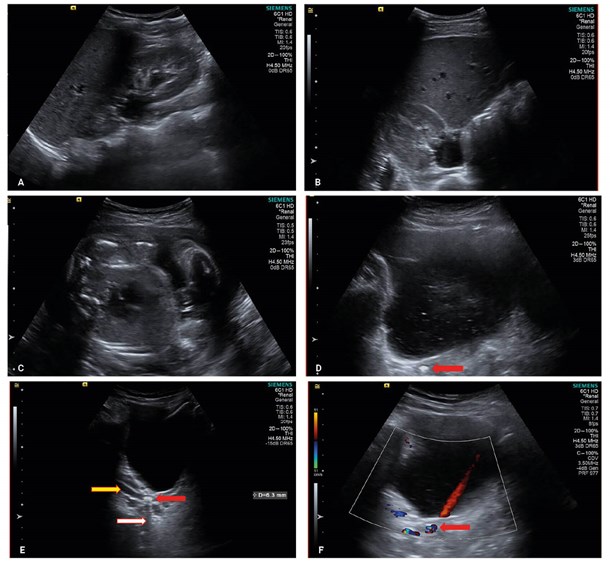

Right hydronephrosis secondary to a 6mm distal ureteric stone during pregnancy.

A and B – Right hydronephrosis.

C – Gravid uterus with 25-week-old foetus.

D – Stone in right distal ureter (red arrow).

E – Stone demonstrating twinkle artefact. Ureteric Jet visible in bladder.

F – Stone (red arrow) with post-acoustic shadow (white arrow) and upstream ureteric dilatation (yellow arrow).